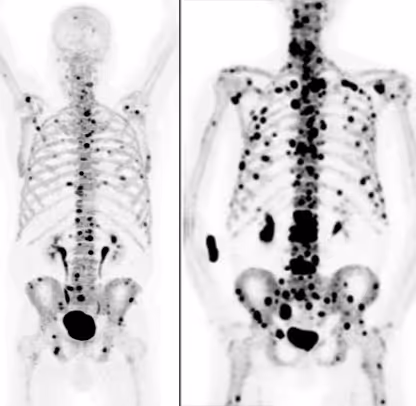

This confirmation is obtained through PSMA PET/CT. This specialized nuclear medicine examination shows whether and to what extent tumor lesions take up PSMA. At the same time, it reveals where active metastases are located in the body.

Only if imaging demonstrates clear PSMA uptake in the tumor lesions is the therapy considered biologically appropriate. If this expression is absent or only minimal, the effectiveness of the treatment is limited or not expected.